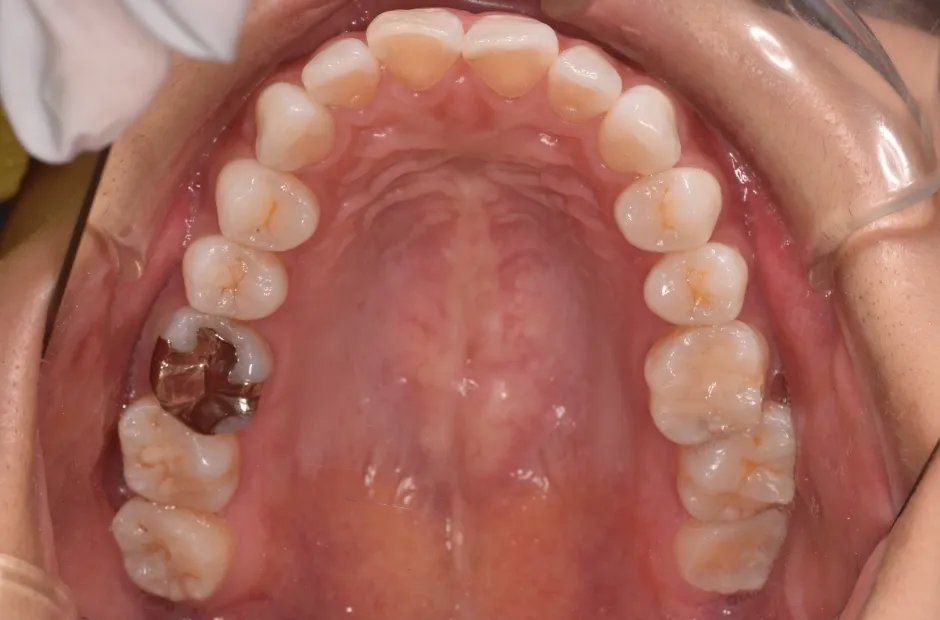

叢生

| 診断名・主訴 | 叢生 |

|---|---|

| 年齢・性別 | 43歳・女性 |

| 治療期間・回数 | 2年7か月 27回 |

| 治療に用いた主な装置 | 舌側矯正 |

| 抜歯部位 | 両顎4,4 |

| 治療費 | 100万円(税抜) |

| リスク・副作用 | 装置による違和感・疼痛・歯肉退縮・歯根吸収・虫歯のリスクなど |

治療前

治療中

治療後